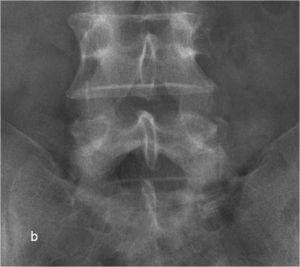

При рентгенографии (Рис.7) и МРТ (Рис.8) поясничного отдела позвоночника выявляется дегенеративный ретролистез L5 позвонка, секвестрированная  парамедианная грыжа мп диска L5-S1  слева.

Рис. 8а. Рентгенограмма поясничного отдела позвоночника в боковой (а) и прямой (b) проекциях до операции. Стрелкой показано смещение тела L5 позвонка кзади. Рис. 8b. Рентгенограмма поясничного отдела позвоночника в боковой (а) и прямой (b) проекциях до операции. Стрелкой показано смещение тела L5 позвонка кзади.

Рис. 7а,b. Рентгенограмма поясничного отдела позвоночника в боковой (а) и прямой (b) проекциях до операции. Стрелкой показано смещение тела L5 позвонка кзади.